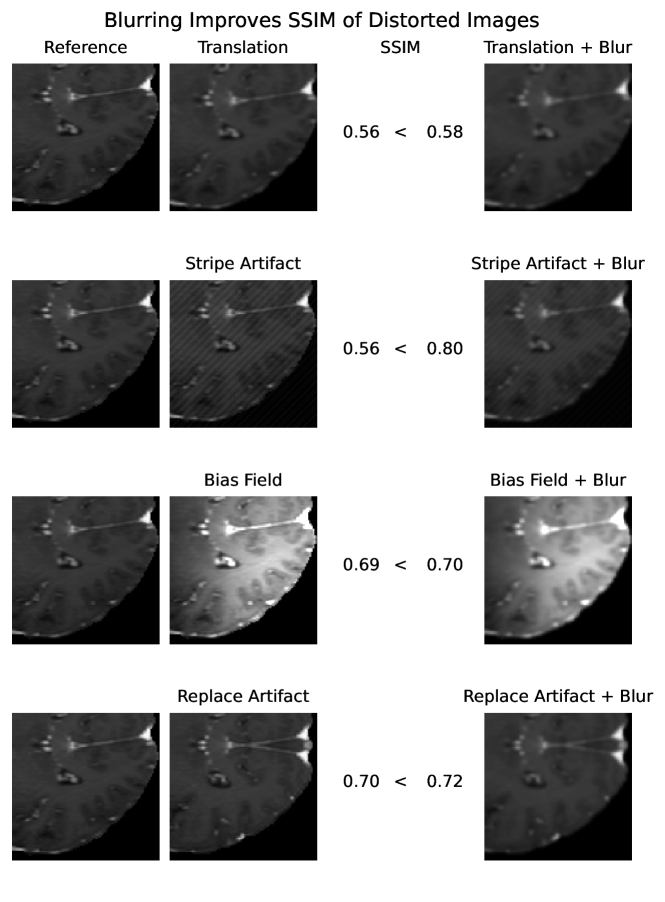

SSIM similarity scores for strong blurring are very high, compared to most other distortions.

5 Adverse Examples

In the following, special characteristics of the analyzed metrics, which can be derived from their definition or the experimental results above, are show-cased. We present adverse examples (see Fig. 2-6), where similarity metrics do not perform as intended or expected.

The experiments and adverse examples demonstrate specific strengths and weaknesses of the analyzed metrics. Although SSIM and PSNR are frequently used for the evaluation of synthetic MR images, they are strongly decreased by constant intensity shifts if no normalization is applied. PSNR is very dependent on the kind of normalization, which complicates its use as a comprehensive metric for comparing studies of different authors. SSIM underestimates blurring and thereby favors blurred or additionally blurred images over other distortions.